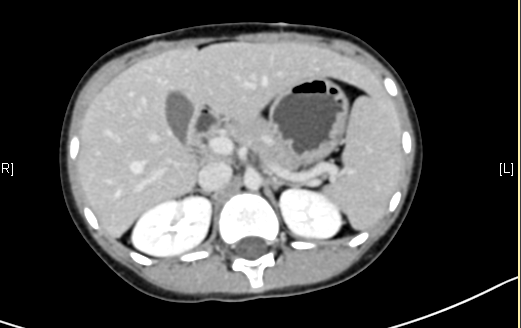

术前CT检查:

动脉期

腹部超声示:肝内包块。腹部CT:肝脏占位,血管瘤?上腹部增强CT:肝左内叶-右前叶交界区、尾叶囊实性团块影,考虑肿瘤(胆管囊腺瘤?间叶性错构瘤?)